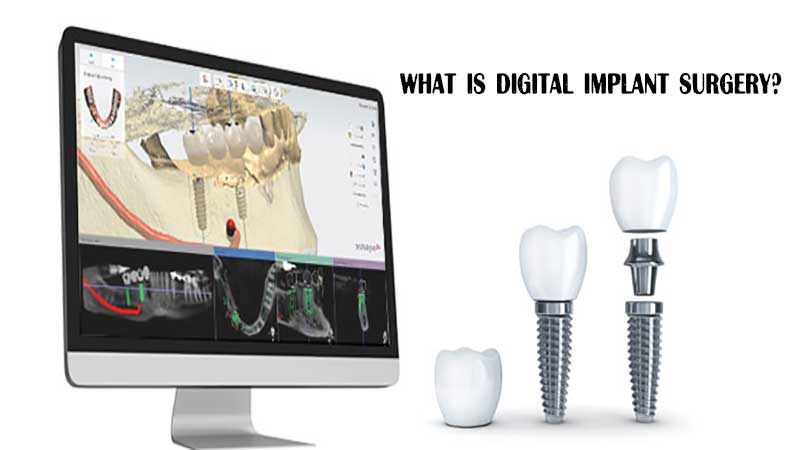

جراحی ایمپلنت دیجیتال چیست؟

جراحی ایمپلنت دیجیتال چیست؟

جراحی ایمپلنت دیجیتال چیست؟

جراحی ایمپلنت دیجیتال (که به آن جراحی ایمپلنت با هدایت دیجیتال نیز گفته میشود) از یک شبیهسازی کامپیوتری سه بعدی برای بررسی وضعیت استخوان و موقعیت عصبی استفاده میکند. با استفاده از این اطلاعات، یک دندانپزشک زیبایی معتبر میتواند با حداقل برش جراحی را انجام دهد. از آنجا که عمل جراحی ایمپلنت دیجیتال بر ایجاد کوچکترین برشِ ممکن تمرکز دارد. درد در مقایسه با جراحی ایمپلنت سنتی به شدت کمتر خواهد بود.

در حین انجام عملیات دندانپزشکی، از یک راهنمای دقیق بر روی دندانها استفاده میشود تا اطمینان حاصل شود که آسیبی به عصب یا دندانهای اطراف وارد نمیشود. این راهنما همچنین به دندانپزشکان کمک میکند تا برشهایی دقیق و در عین حال کوچک را برای جایگذاری ایمپلنت دندان ایجاد کنند.

اکنون با روش جدید کاشت دندان دیجیتال، پزشکان میتوانند سریعتر و راحتتر از گذشته فرآیند شما را انجام دهند.